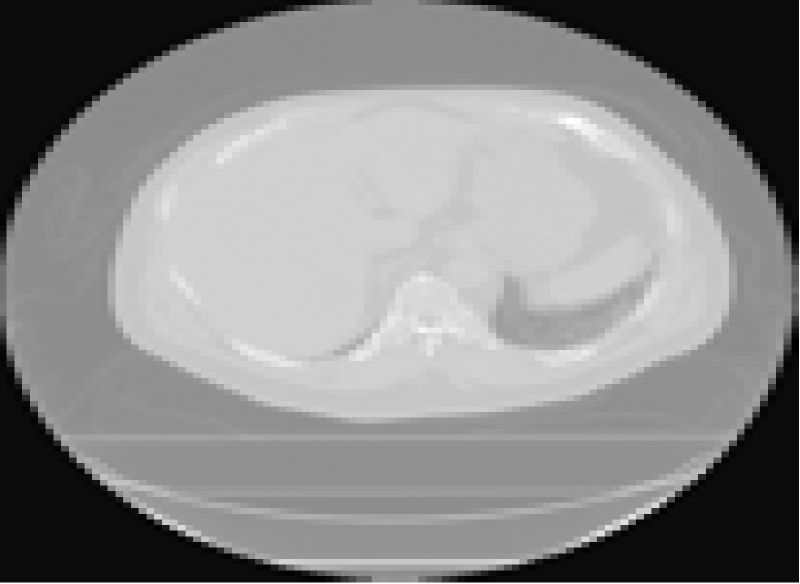

In this section, we consider the application of the methodology to X-ray computed tomography (CT) imaging [49, 50]. First, we evaluate the performance of the proposed methods on real tomographic X-ray data of an emoji phantom measured at the University of Helsinki [51]. The dataset consists of 33-point time series of the X-ray sinogram of an emoji made of small squared ceramic stones. In the sequence, the emoji transforms from a face with closed eyes and a straight mouth to a face with smiling eyes and mouth. Typically, we have a sequence of square X-ray images of size with , which we are interested in reconstructing from low-dose observations taken from a limited number of angles. These low-dose observations can be modeled by the measurement matrix which describes line integrals through the object (i.e., Radon transform).

Fig. 8 shows the CT reconstruction results for the emoji motion dataset, obtained by KS-ADMM. We set the parameters to , , , and . The analysis operator consists of all the vertical and horizontal gradients (one step differences), which corresponds to so called TV regularization [21]. The number of measurements that correspond to or projections are and , respectively. Although there is no ground truth to compare the qualitative results, we can observe the visual results from different numbers of projections. When the number of projections is , the method provides good reconstruction results with iterations. We see that the 30-projection results suffer from the block artifacts as a consequence of the reduction in dose.

Furthermore, we validate the effectiveness of the proposed method on the real inhalation (iBH-CT) and exhalation (eBH-CT) breath-hold CT images, which was acquired as part of the National Heart Lung Blood Institute COPDgene study [52]. The dataset consists of 10 expiratory phase images of the segmented lung voxels. In detail, the parameters are , , , , , and the numbers of measurements are and , corresponding to and projections. The ground truth and the reconstruction results are shown in Fig. 9. By visually comparing the results, we observe that moving from to projection provides much more drastic change. For example, some additional artifacts exist, but the result with the setting and is still very much acceptable (see the third column in Fig. 9). The results show that our methods still successfully preserve temporal information when the number of projections is .

In the two experiments, we used a stationary Kalman filter and smoother to implement the optimization. We pre-computed all the gains before the iteration, which significantly speeded up the computations in tomographic reconstruction. We report CPU time (seconds) in Table IV. Table IV shows that KS-ADMM achieves significantly lower CPU time than the batch ADMM although the visual quality of all the reconstructions is equal. For example, in emoji motion dataset, when , ADMM takes three time longer than our proposed method. In the lung dataset, when and , KS-ADMM seems to be promising to provide computationally efficient reconstruction.